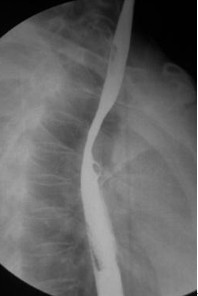

女,51岁,以“进行性吞咽困难1年”为主诉于2007年2月19日入院。钡餐造影、胃镜示食管上段占位性病变,确诊为食道鳞癌(图1),拒绝手术,行放疗+今又生治疗。食道镜下瘤内注射今又生,1×1012VP/次/周×6,放疗在今又生注射3 d后开始,采用常规分割三野等中心照射,剂量65cGY。治疗结束后4周,食管X线、胸部CT显示肿瘤完全消退(图4-5)。

治疗前

放疗40GY+今又生4支后

放疗65GY +今又生6支后

放疗结束4周后